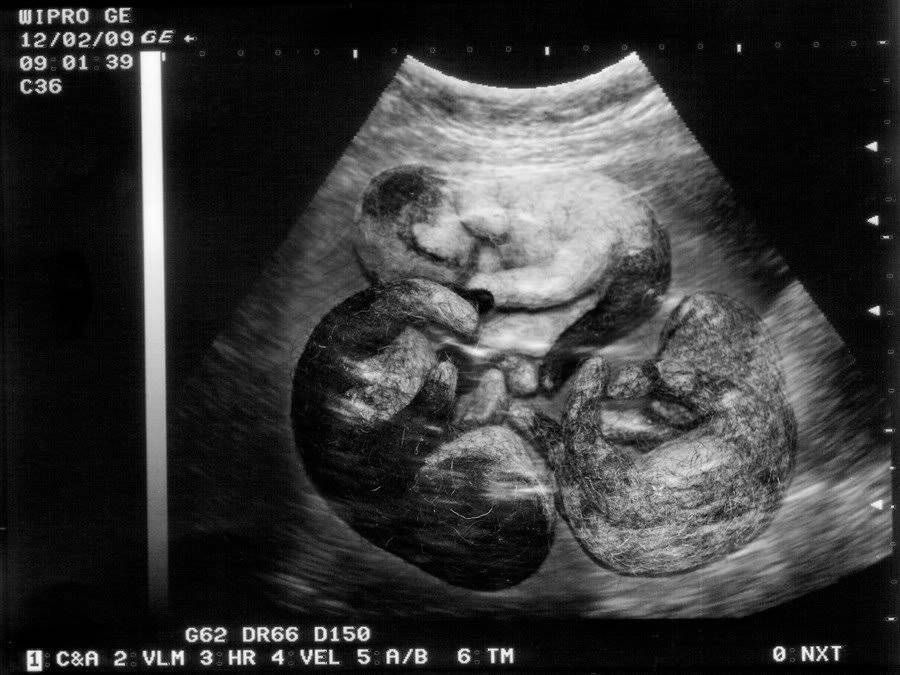

- Научный метод считается самым точным из всех существующих и проводится за неделю-две до предстоящих родов на ультразвуковом оборудовании.

Наиболее точный метод определения количества котят – УЗИ

И, наконец, самый последний вопрос, ответ на который хотят получить все заводчики породистых (и не очень) кошек, без исключения. И звучит он приблизительно так: а можно ли узнать до завершения родов, сколько котят родит кошка? Да, можно. Только не стоит пытаться делать это органолептическим путём. При использовании метода пальпации ошибаются даже профессионалы. К тому же есть большая вероятность, что кошке не понравится подобная процедура. Единственный метод, который точно определит количество ещё не родившихся кошачьих малышей и не причинит вашей питомице серьёзного дискомфорта, является ультразвуковое исследование (УЗИ). Сроки его проведения лучше согласовать с ветеринарным врачом.